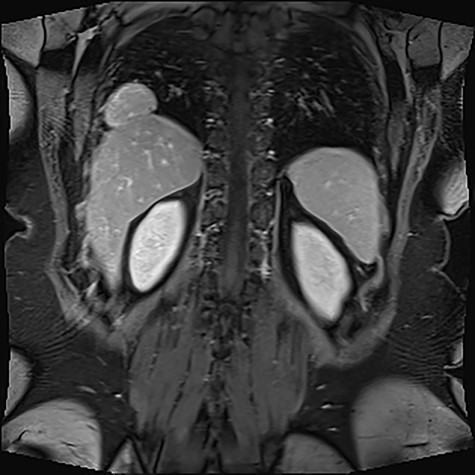

Given the ambiguous morphology of the lesions and the inconclusive CT and USS findings, an abdominal MRI was arranged. The MRI showed a distended gallbladder with multiple calculi in the lumen measuring 2–3 mm. In addition, segmental focal concentric thickening consistent with adenomyomatosis was identified at the body and fundus of the gallbladder. Notably, a multilobulated solid lesion measuring 5.7 × 2.9 × 3.6 cm was described in the right hemithorax, closely abutting the right costophrenic recess (Fig. 1). The mass appeared to be continuous with the right hepatic lobe via a narrow pedicle and demonstrated similar architecture and vessel continuity with the liver.

Multilobulated solid lesion measuring 5.7 × 2.9 × 3.6 cm seen in the right hemithorax adjacent to a right costophrenic recess, closely abutting the liver and appears to be continuous with the liver parenchyma with a narrow pedicle/area of contact.